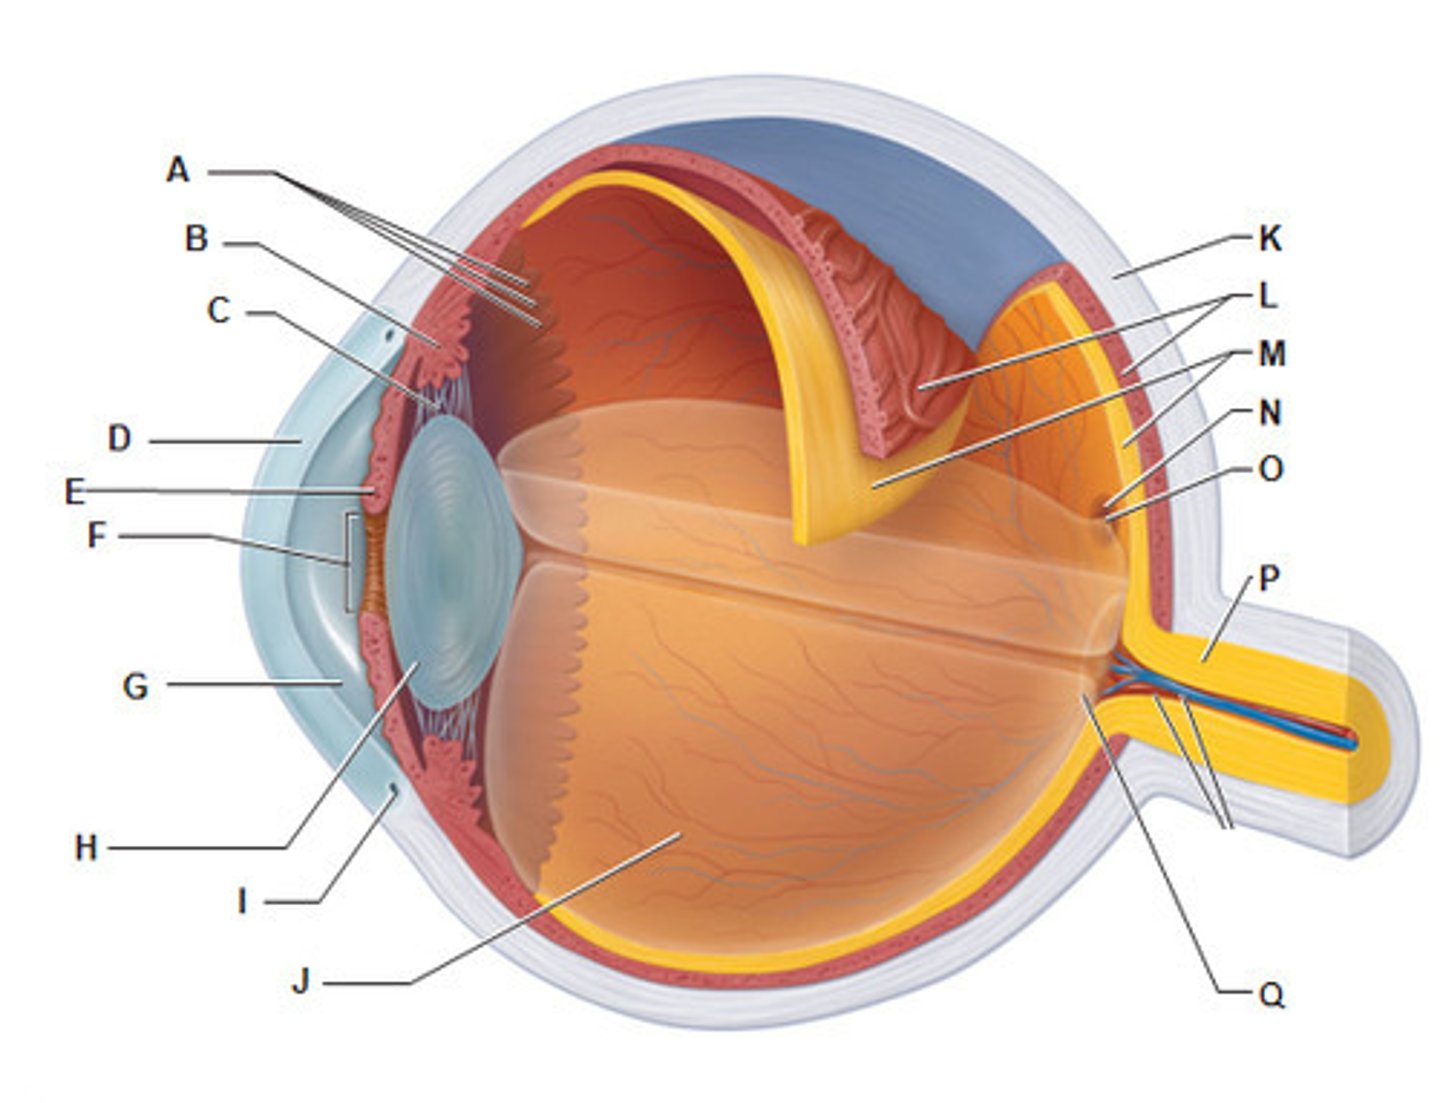

anterior cavity (of eye)

iris

B

choroid

L

ciliary body

B

ciliary process

conjunctiva

cornea

D

fovea centralis

suspensory ligaments

C

vitreous humor

lens

H

macula lutea

posterior cavity (of eye)

pupil

F

retina

M

sclera

optic nerve